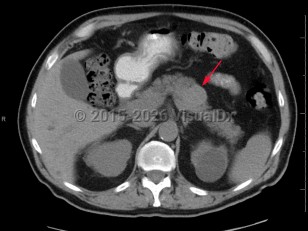

Pancreatic carcinoma

Patients typically present with advanced disease, as signs and symptoms can be very subtle, especially early in the disease. Classically described signs and symptoms include pain, jaundice, and weight loss.